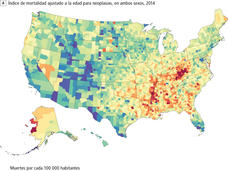

Descienden los índices de mortalidad por cáncer en EE. UU., pero algunas regiones están atrasadas, indica un estudio

Un estudio de datos de mortalidad de todo el país encontró que, mientras las muertes por cáncer disminuyeron en EE. UU. entre 1980 y 2014, las desigualdades se mantuvieron, y en 160 condados la mortalidad por cáncer se elevó considerablemente.